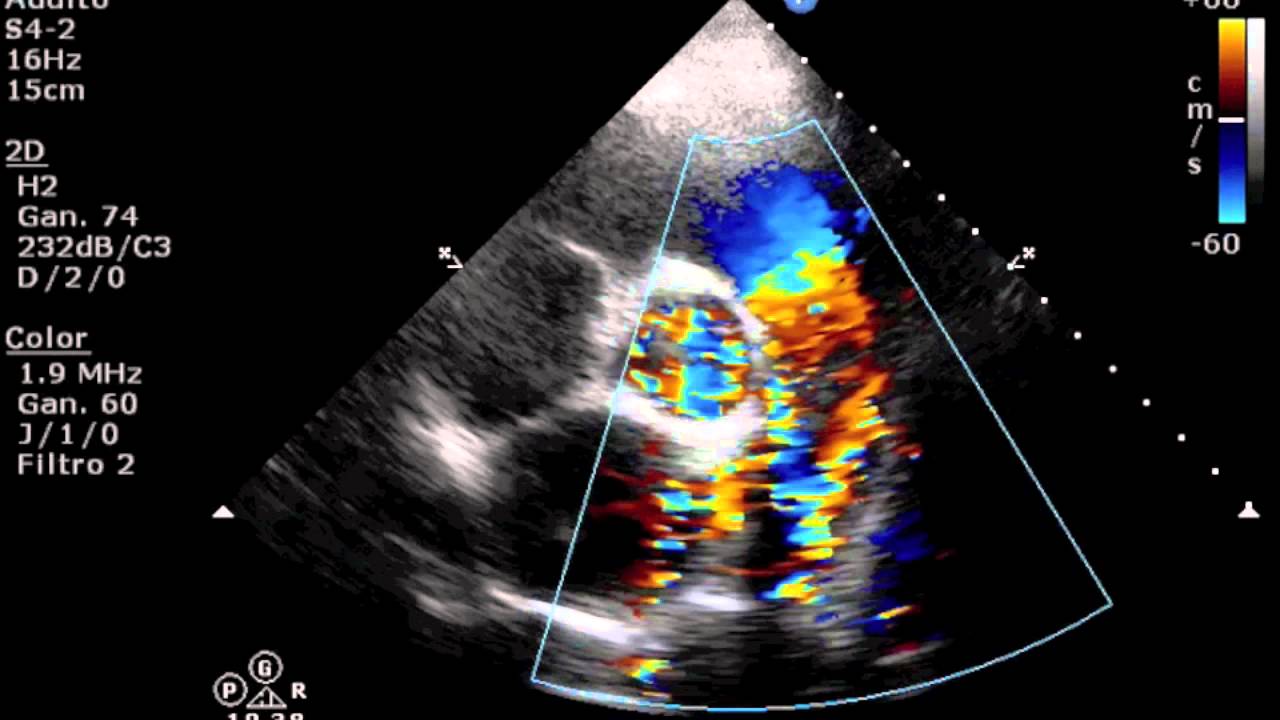

tal e E então comecei pela via de saída né Achei bem normal o ato Aparecida um pouquinho de homem realmente né Com relação à horta aqui na via de saída Ok mas não me chamou muita atenção a Carol tinha visto aumente deatro também no exame dela quando eu me disse vão ver Não Acabou que nem deu aumento aí fui aí primeira coisa que me chamou atenção foi a insuficiência pulmonar amor tem paciente que tem às vezes fisiológicas vezes já nasce com muita ciência sim mas é uma extensão maior lona aqui né e o diâmetro da

artéria pulmonar também tava esquisito e tá vendo tinham é uma turbulência aqui ó essa turbulência dentro da artéria com o ar me chamou atenção de cara Carol também viu isso ela viu que tinha alguma coisa estranha com fluxo pulmonar aí é mais uma foto né da Justiça pulmonar E aí você também passar pros vídeos aqui no vídeo depois aí eu tirei uma foto do fluxo pulmonar nas estude né do VD eu vi que dava para ver o filme Ok mas aí tem alguma coisa vermelhinha saindo daqui do fundo tá vendo o que fazer uma turbulência

do lado desse lado aqui da artéria aí tem alguma coisa errada aí a seguir o exame aí eu falei já pus a pergunta que será que é um PDA não tá a característica que não uma um jato continuo mas eu via toda hora alguma coisa turbilhando aqui e não era o achei isso é pulmonar e não era uma estenose pulmonar Porque daí eu eu fiz eu peguei e essa imagem aqui ó e diz que pus a amostra para registrar o fluxo ar bem no cantinho da artéria aqui no lado esquerdo da minha tela é e

tenta tentando fugir da da turbulência aí ó pois bem do que eu tinha consegui pegar o fluxo pulmonar razoavelmente preciso tá um pouco alto Ok mas não é uma estenose pulmonar é bom presta alto aqui pode ter uma sobrecarga de volume né pensei ser um PDA vai ter sobrecarga de volume vamos lá aqui tem um vídeo não dá para ver muito bem à insuficiência pulmonar né e eu vejo eu já tinha vermelhinha aqui ó hoje novo a China que na hora da Sister ele aparece mais fácil né mas ele ele via de regra ele tá

quase toda vez mas ele é mais intenso Em algum momento e menos intenso em outro E aí ele acompanha adiasse ver que o aí vocês pulmonar e na diástole também é mais visível né de Astro vai ter mais um vídeo aqui e eu sem querer que eu vou ver E aí tem momento que é muito ó viu é muito caro por isso que já pegou um PDA e vice já tô aqui vermelho turbulento para cima que muito facilmente eu vi aí ficou bem mais jovem para mim eu já tinha saindo daqui bem na seta do

meu mouse aqui ó dá para ver eu já tinha vermelhinho saindo aqui ó você vê que ele não tem a ver com fluxo pulmonar ele é muito mais forte nade ar na sístole né quando da contração ele também aparece mais mas ele persiste durante a diástole de novo pode ver ele persiste junto no mesmo momento que é insuficiência pulmonares está acontecendo Então ele tava assistindo na diástole falei bom aqui eu já não tive muita dúvida que era um pedaço aí eu esperava algumas confirmações durante primeiro a turbulência né tentei registrar aqui aí eu coloquei o

eu não estava convencido que o átrio o ato não tava tão aumentado EA insuficiência da me troca Carol tinha visto nos vídeos dela Era exatamente o que eu via era mas você ser pequena eu falei não não tem alguma coisa errada aí tem aquela turbulência na artéria pulmonar e tal aí nós marcamos a reavaliação porque não tava batendo é só bater o raciocínio depois que a gente começou a olhar de novo aqui eu mudei um pouco a configuração do Collor dá para ver melhor eu já to subindo aqui em amarelo vendo e ele vai diminuir

a eles vai de novo forte vai diminuindo de mais forte é porque a pressão tá mais perto de equalizar óleo J vermelho aqui bem na base aqui da artéria pulmonar eu já tô bem sim eu não consigo pausar e esse jato aqui ó Tá eu já to subindo aqui nesse momento tá vendo que é que tá na diastro eu tenho esquecido pulmonar aqui também certo É mas o vídeo que te ver e eu tô com um pouco de artefatos aqui no colo né mas eu tô tentando pegar o jato bem mais evidenciar mais o jato

o ok toda essa área aqui ó a laranja eu já to subindo tá e o fluxo Azul das histórias a da artéria pulmonar descendo tá é bem comum a gente ver isso quando é um pedal mais novo dizer assim os olhos já estão aqui ó vermelhão subindo aqui aqui na diástole também a de Aço eu vi é bem melhor porque não tem as isso não tem aquele Jato da artéria pulmonar descendo né é bem mais fácil de ver um PDA quando você tá com ele mais novo 10 assim ó se alguém alguém com a dúvida